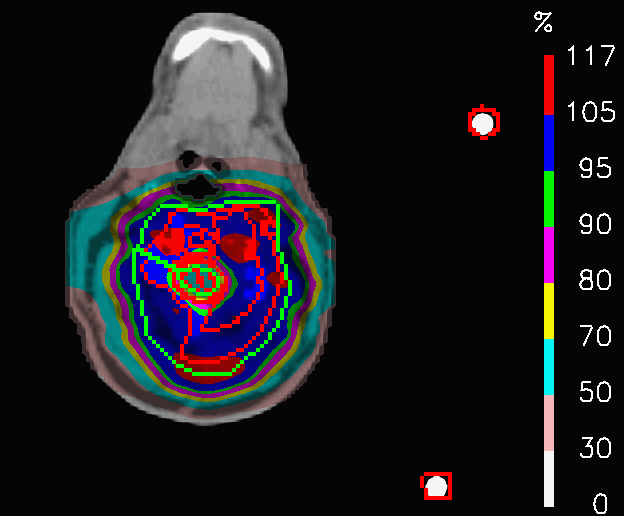

Refer to caption

Figure 6: Head and neck tumour: azimuthal CT slice showing the fifth intracranial field added for PLAN-OL-2.

One common indication for proton therapy centers is represented by tumours extending both in the head and neck. As the tumour extends over a relatively big area, the treatment can result rather toxic for many organs at risk. These cases are usually treated with four fields, as shown in Fig.5: two coming from the front, aimed at covering the target volume at the level of the shoulders, two coming from behind, supposed to deliver the dose in the head part of the tumour. The drawback of this geometry is that, despite the dose constraints, the front fields irradiate OARs inside the head and, in the same way, the back fields release high dose to the shoulders, without being crucial for target coverage in that point.

The OL penalization is, here, exploited to switch off the fields in selected areas and to test a new field geometry. In PLAN-OL-1, two artificial VOIs were drawn at the level if the shoulders and were assigned with OL = 1, to switch off, respectively, the posterior fields irradiating that area. In PLAN-OL-2, two addional artificial VOIs are created at the level of the head and set with OL = 1, to switch off the anteriori fields in the part of the patient volume and a fifth intra-cranial field is added to compensate for the target coverage, as shown in Fig.6.